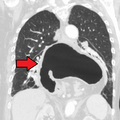

A large hiatus hernia as seen on CT imaging